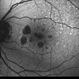

By Gregg T. Kokame, MD, MMM, FASRS

Co-author(s): James C. Lai, MD, Retina Conslutants of Hawaii - Uploaded on Oct 12, 2012.

- geographic atrophy

- Jaclyn Pisano, Retina Consultants of Hawaii

Fundus camera

Zeiss FF-450 plus - Description

- AMD, geographic atrophy